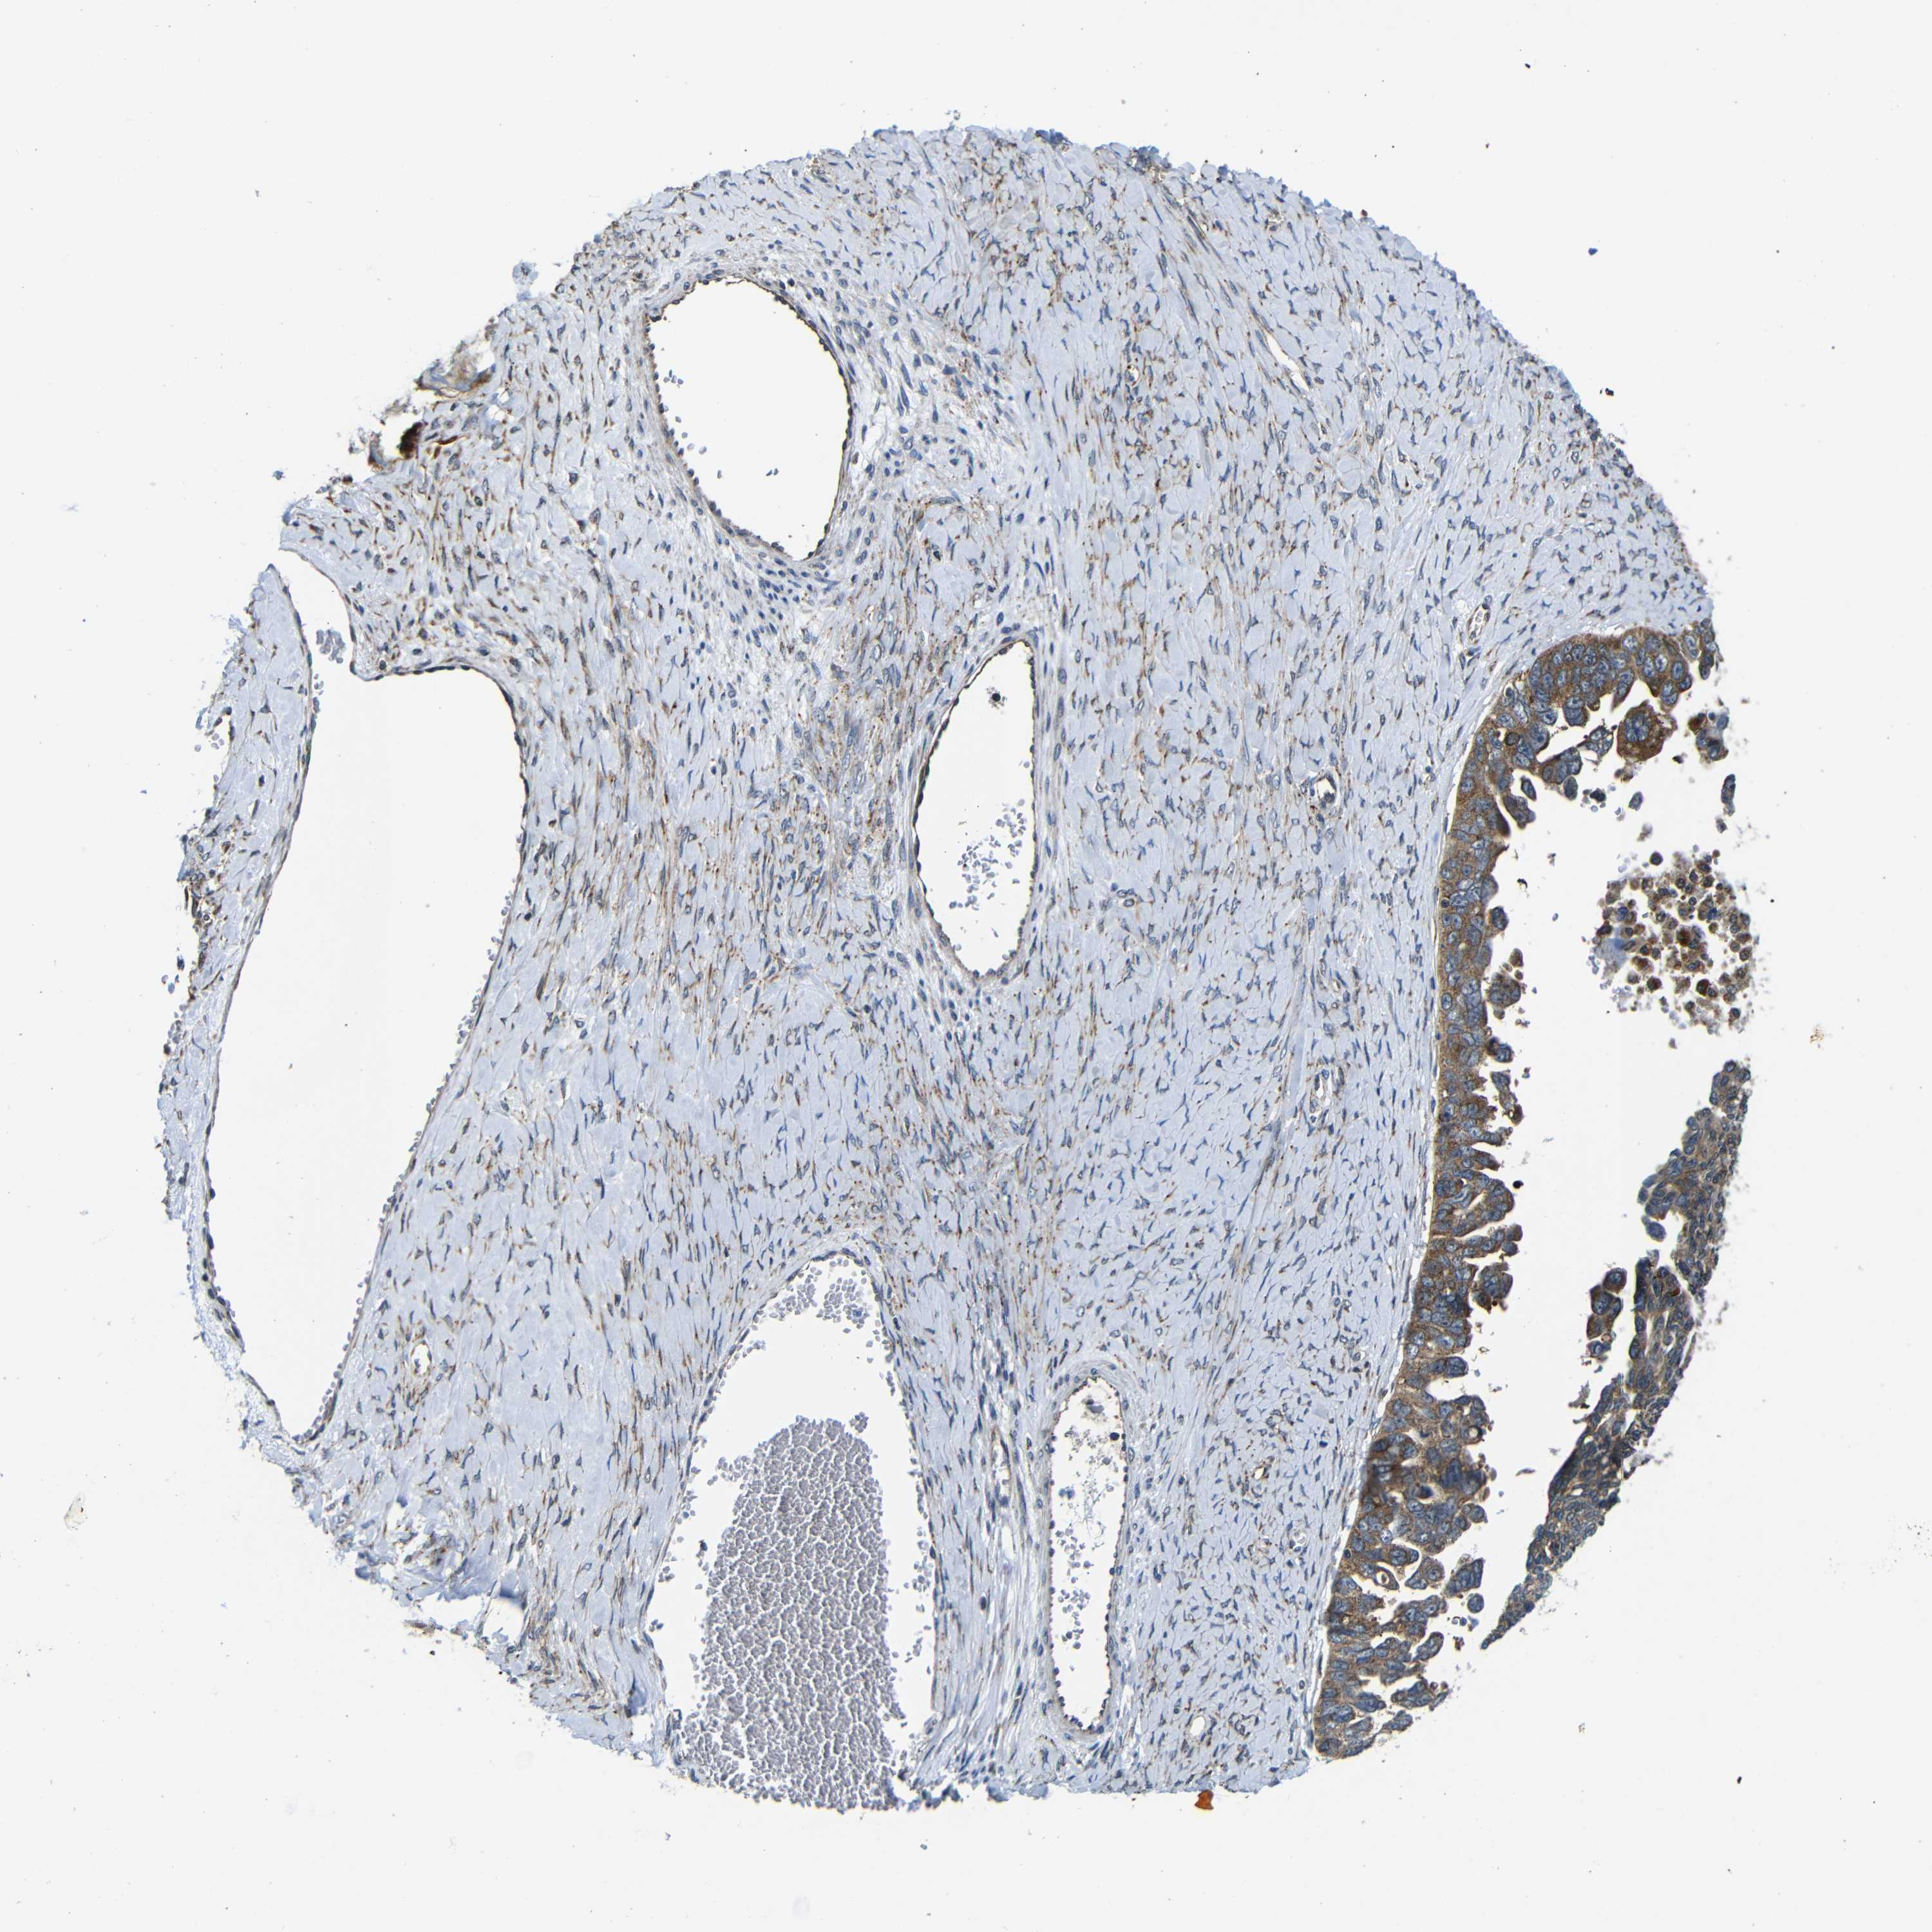

OVARIAN CANCER - Protein expressioni

A mouse-over function shows sample information and annotation data. Click on an image to view it in a full screen mode. Samples can be filtered based on level of antibody staining by selecting one or several of the following categories: high, medium, low and not detected. The assay and annotation is described here.

Note that samples used for immunohistochemistry by the Human Protein Atlas do not correspond to samples in the TCGA dataset.

Antibody stainingi

Antibody staining in the annotated cell types in the current human tissue is reported as not detected, low, medium, or high, based on conventional immunohistochemistry profiling in selected tissues. This score is based on the combination of the staining intensity and fraction of stained cells.

Each image is clickable and will lead to virtual microscopy that enables deeper exploration of all samples and also displays staining intensity scores, fraction scores and subcellular localization as well as patient and tissue information for each sample.

Antibody CAB012476

Staining

High

Medium

Low

Not detected

Intensity

Strong

Moderate

Weak

Negative

Quantity

>75%

75%-25%

<25%

None

Location

Nuclear

Cytoplasmic/membranous

Cytoplasmic/membranous,nuclear

Cystadenocarcinoma, serous, NOS

Carcinoma, endometroid

Cystadenocarcinoma, mucinous, NOS

Carcinoma, NOS